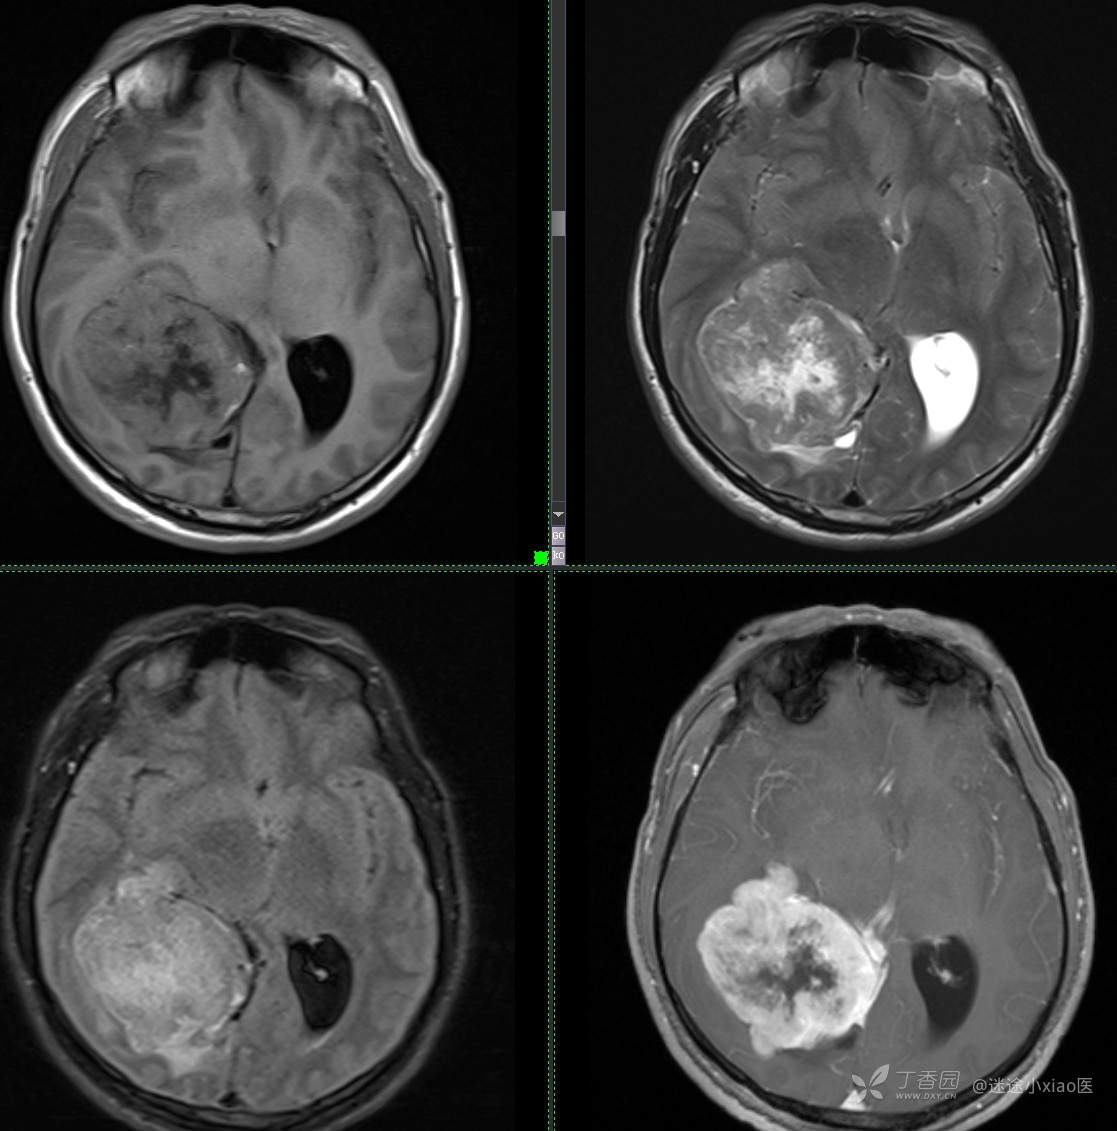

患者年龄:43

患者性别:男

简要病史:头痛3月余,查体无殊